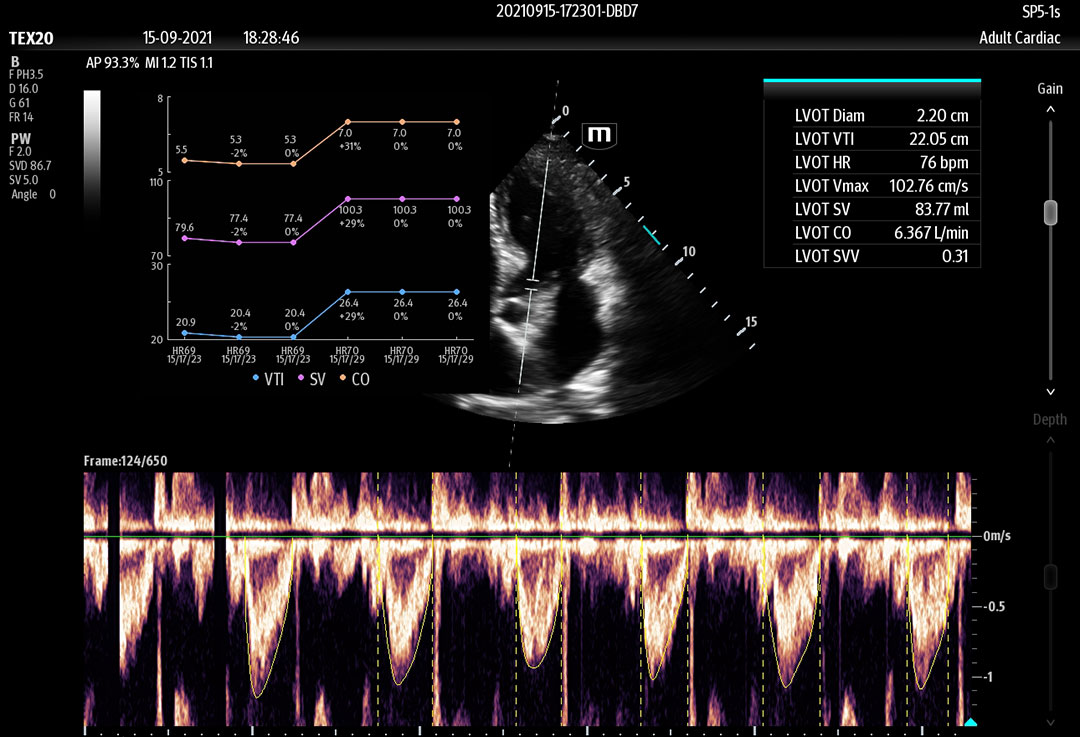

The technology-rich TE X Ultrasound System gives clinicians access to market-leading artificial intelligence (AI)-powered Smart Tools, an ergonomically designed system, and proprietary software-based beamformer Zone Sonography Technology+ (ZST+). By incorporating these elements, the TE X Ultrasound System provides access to advanced diagnostic data, the ability to adapt to the various clinical scenarios at point of care, and best-in-class imaging to help them provide a higher standard of care.